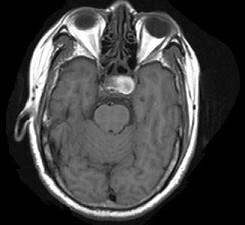

问题 男性,55岁,头痛1年余,2个小时前突然出现剧烈头痛,MRI检查如图所示,最可能的诊断为()

选项 A.垂体瘤 B.脑膜瘤 C.颅咽管瘤 D.垂体瘤并卒中 E.动脉瘤

答案 D